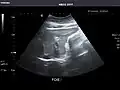

Abdominal Ultrasound (Full Exam)

STRUCTURED REPORT

(Technique: Transabdominal ultrasonography; Device: Toshiba Aplio XG)

Liver: Diffusely homogeneous and normal in echogenicity. No focal mass or contour nodularity. No intrahepatic biliary ductal dilatation.

Portal Vein: Patent main portal vein.

Gallbladder: No stones, wall thickening, or pericholecystic fluid.

Common Bile Duct: Nondilated measuring 1.3 mm at the level of the porta hepatis.

Pancreas: Visualized portions unremarkable.

Spleen: Normal in size.

Kidneys: Right and left kidneys measure 11.5 cm and 12 cm in length respectively. No hydronephrosis. Small left lower pole kidney cyst.

Ascites: None.

Aorta: Visualized portions normal in caliber, 16 x 15 mm.

IVC: Normal.

IMPRESSION:

Normal abdominal ultrasound.

Right kidney -